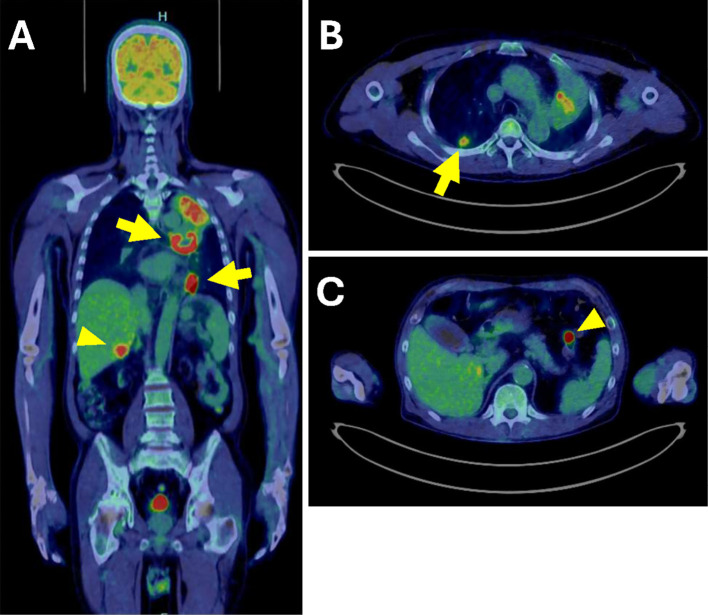

移植后淋巴细胞增生性疾病(PTLD)影响0.8-2.5%的肾移植患者,发病率在移植后1年和10-14年达到高峰。非常晚发性PTLD (VL-PTLD)可在移植后10年以上发生,据报道可达30年,但其特征尚不清楚。61岁男性,肾移植45年后出现PTLD,表现为发热、呼吸急促。计算机断层扫描显示肺和肝脏肿块,活检证实为IVB期单纯性PTLD。尽管获得了初步改善,但患者于第66天死亡。VL-PTLD可能不同于早发性或晚发性PTLD,因此需要进一步研究相关风险和管理。

Post-transplant lymphoproliferative disorder (PTLD) affects from 0.8-2.5% of kidney transplant patients, with peaks in incidence within 1 year and 10-14 years post-transplant. Very late-onset PTLD (VL-PTLD) can occur over 10 years post-transplant, reportedly up to 30 years, but its characteristics remain unclear. A 61-year-old man developed PTLD 45 years after kidney transplant, presenting with fever and shortness of breath. Computed tomography revealed lung and liver masses and biopsy-confirmed stage IVB monomorphic PTLD. Despite obtaining an initial improvement, the patient died on day 66. VL-PTLD may differ from early- or late-onset PTLD, thus necessitating further research on both the associated risks and management.